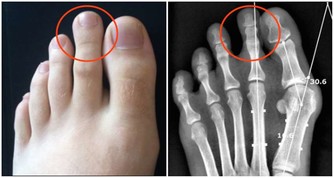

7.善感多疑,總是懷疑自己有大病,雖然不斷進行各種檢查,但仍難釋其疑。